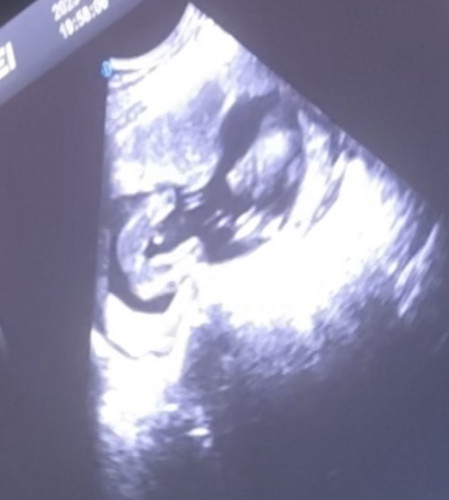

เพศลูก 18 wk

แบบนี้แม่ๆพอมองออกมั้ยคะว่าเพศอะไร

น่าจะเป็นผู้หญิงนะคะ